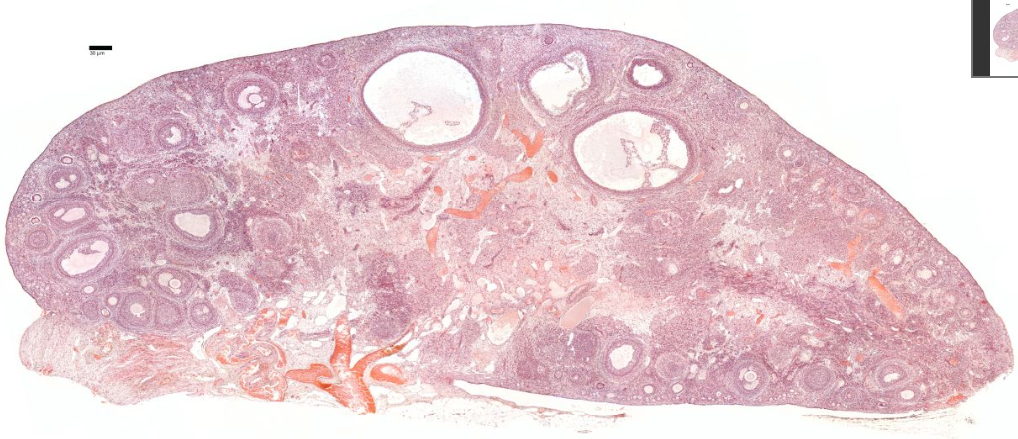

{A diagram of a sectioned ovary (a) shows the different stages of follicle maturation, ovulation, and corpus luteum formation and degeneration. All of the stages and structures shown in this diagram actually would appear at different times during the ovarian cycle and do not occur simultaneously. Follicles are arranged here for easy comparisons. The primordial follicles shown are greatly enlarged. The histologic sections identify primordial follicles (b), a primary follicle (c), a secondary follicle (d), and a large vesicular follicle (e). After ovulation, the portion of the follicle left behind forms the corpus luteum (f), which then degenerates into the corpus albicans (g). All H&E.]